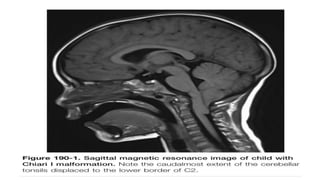

Imaging Chiari I Malformations

• The imaging method of choice is MRI

• The tonsillar herniation was noted to be clearly patho- logic when it

exceeded 5 mm and borderline between 3 and 5 mm.